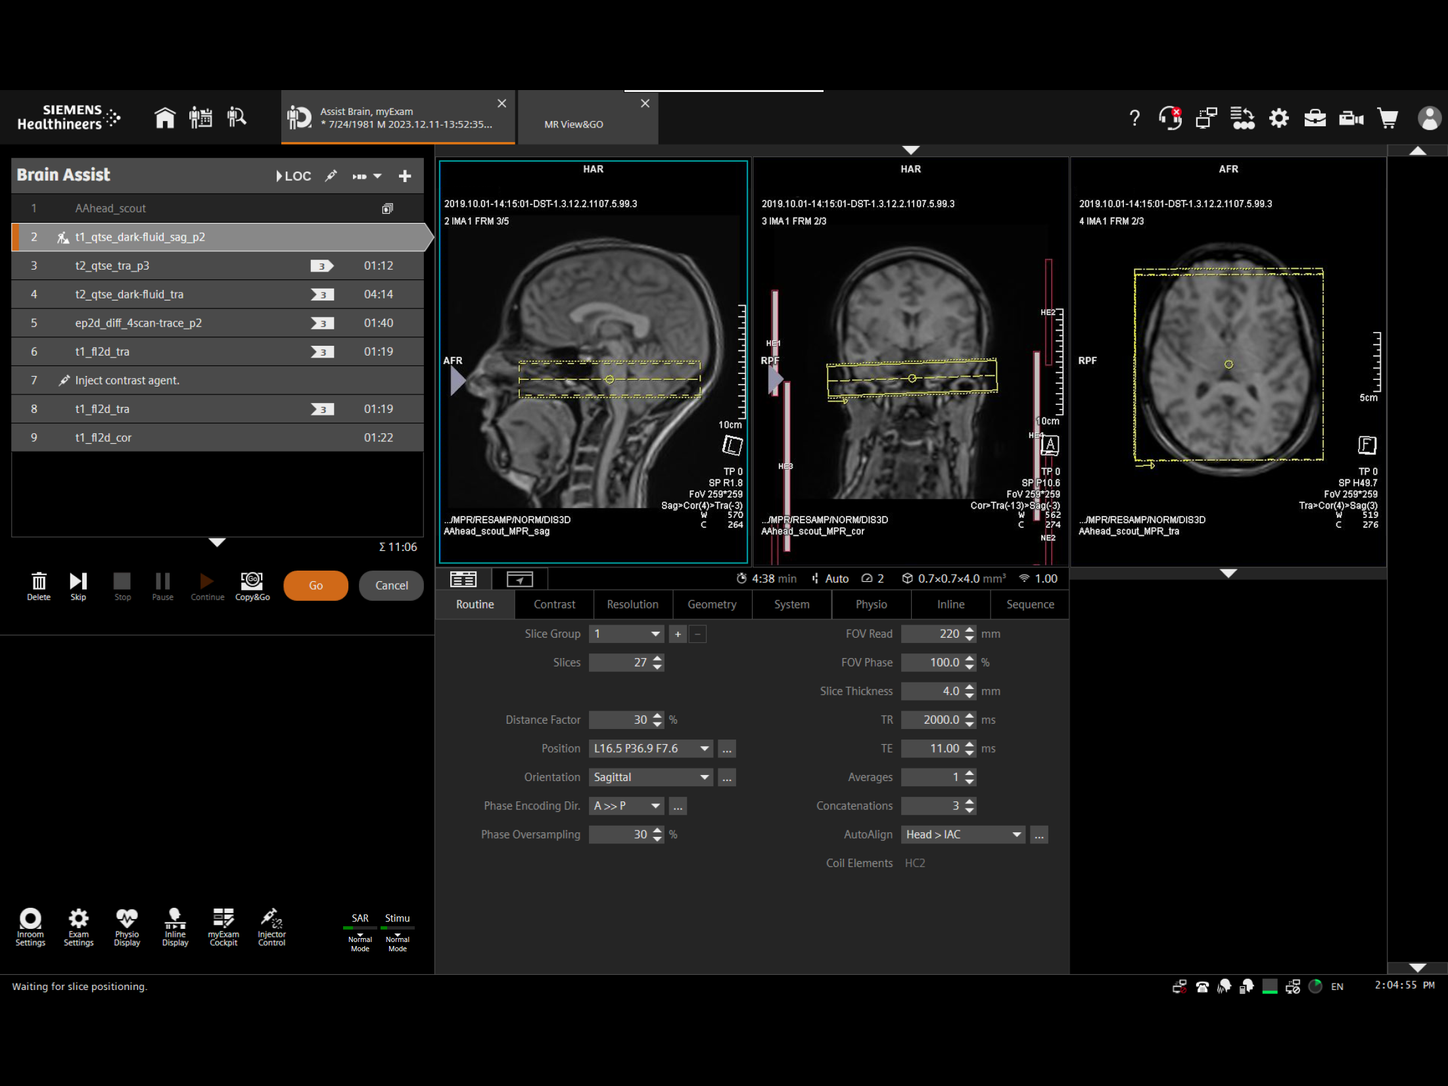

Magnetic Resonance Imaging

Our innovative MRI technologies offer you exceptional image quality, efficiency, and speed, while providing patient friendliness and investment protection. Equipped with these technologies and a very strong global collaboration network, we enable you to lead in MRI.